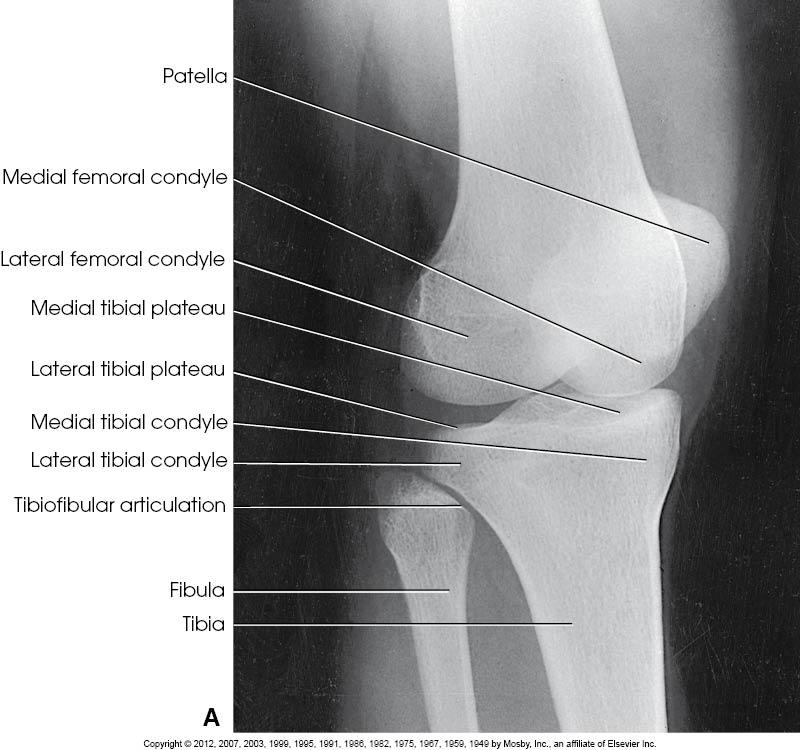

Structures

Shown

• Open knee joint

• Patella superimposed on

femur

• Soft tissue

AP of the Knee